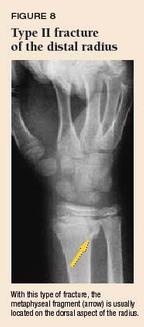

Metaphyseal fractures are fractures that involve the metaphysis of tubular bones . They may occur in paediatric or adult patients . Examples of metaphyseal fractures : adults . surgical neck of humerus fracture ; distal radial fracture ; transtrochanteric fracture ; children . distal radial buckle fracture ; Not all metaphyseal fractures intersect the physis .